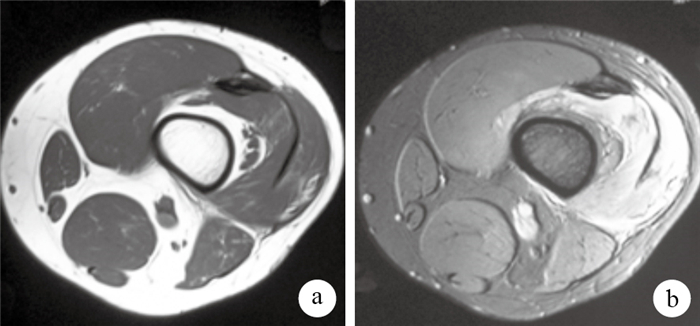

患者男,26歲。因雙大腿腫痛伴膝關節屈曲障礙2 d于2012年10月入院。2 d前患者偶行負重單車鍛煉,持續約40 min。次日出現雙大腿腫脹疼痛,并逐漸出現雙膝關節活動受限,屈曲時癥狀加重,皮色和溫度正常,于大腿腫脹處外用云南白藥后疼痛稍緩解。第3天腫痛癥狀加重,雙下肢無法負重,來我院就診。入院查體:患者雙大腿張力性腫脹,未出現水皰;雙側腹股溝、臀部及膝關節腫脹,浮髕試驗陽性,雙膝痛性活動受限,被動活動膝關節可引起雙側股外側肌劇痛,以左側為著;雙側股外側肌壓痛、質硬;雙下肢針刺覺,遠端肢體皮膚色澤、毛細血管充盈未見明顯異常;雙側足背動脈及脛后動脈搏動有力。腎功能、血常規及出凝血等實驗室檢查未見異常,尿常規提示肌紅蛋白尿。左大腿MRI示:左股骨順序良好,骨質結構完整,骨髓腔內未見異常信號影;股內側肌、股外側肌、股中間肌彌漫性體積增大,信號彌漫性增高;局部肌束膜顯示不清,股內側肌、股外側肌、股中間肌肌間隙消失,肌間隔增粗,股四頭肌下部肌間隔可見長T2液體信號影聚集;股四頭肌肌腱周圍、髕上囊及膝關節腔內可見大量液體信號影(圖 1)。診斷為雙側大腿骨筋膜室綜合征。